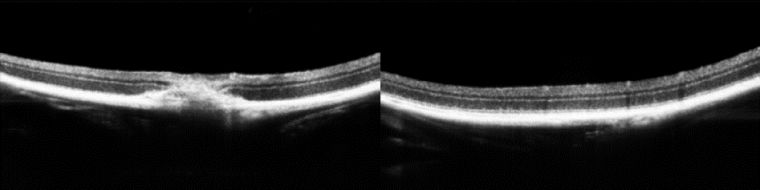

视网膜、角膜OCT断层图---可定量分析

大鼠眼睛视网膜和脉络膜微血管结构

研究青光眼方向---眼压对视网膜和脉络膜影响